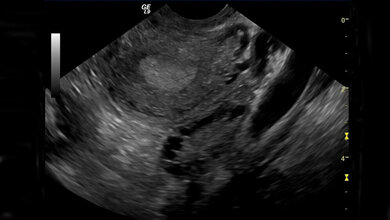

Dieser Frage sind die Forscher im Mausversuch genauer nachgegangen: Sie fanden heraus, dass Mäuse, denen eine Kopie des Wt1-Gens fehlte, deutlich weniger Nachkommen als ihre Wildtyp-Verwandten bekamen. Darüber hinaus entdeckten sie, dass es die Aktivität von Wt1 im Eileiter ist, die die Fruchtbarkeit steuert. Der Eileiter ist für den Transport der reifen Eizelle vom Eierstock in die Gebärmutter verantwortlich. In ihm findet auch die Befruchtung der Eizelle durch ein Spermium statt. Wurde die Eizelle befruchtet, wandert sie weiter durch den Eileiter hindurch bis in die Gebärmutter, wobei sie sich immer weiter teilt und entwickelt. „Dieser Prozess muss sehr kontrolliert ablaufen“, erklärt Prof. Christoph Englert, Forschungsgruppenleiter am FLI, „denn entwickelt sich der Embryo zu schnell, dann droht eine Schwangerschaft im Eileiter; erfolgt die Entwicklung des Embryos zu langsam, dann kann er sich nicht in der Gebärmutter einnisten und wird abgestoßen. Die Kommunikation zwischen dem mütterlichen Gewebe und dem Embryo ist also enorm wichtig für den Erfolg einer Schwangerschaft“, so der Molekulargenetiker weiter.